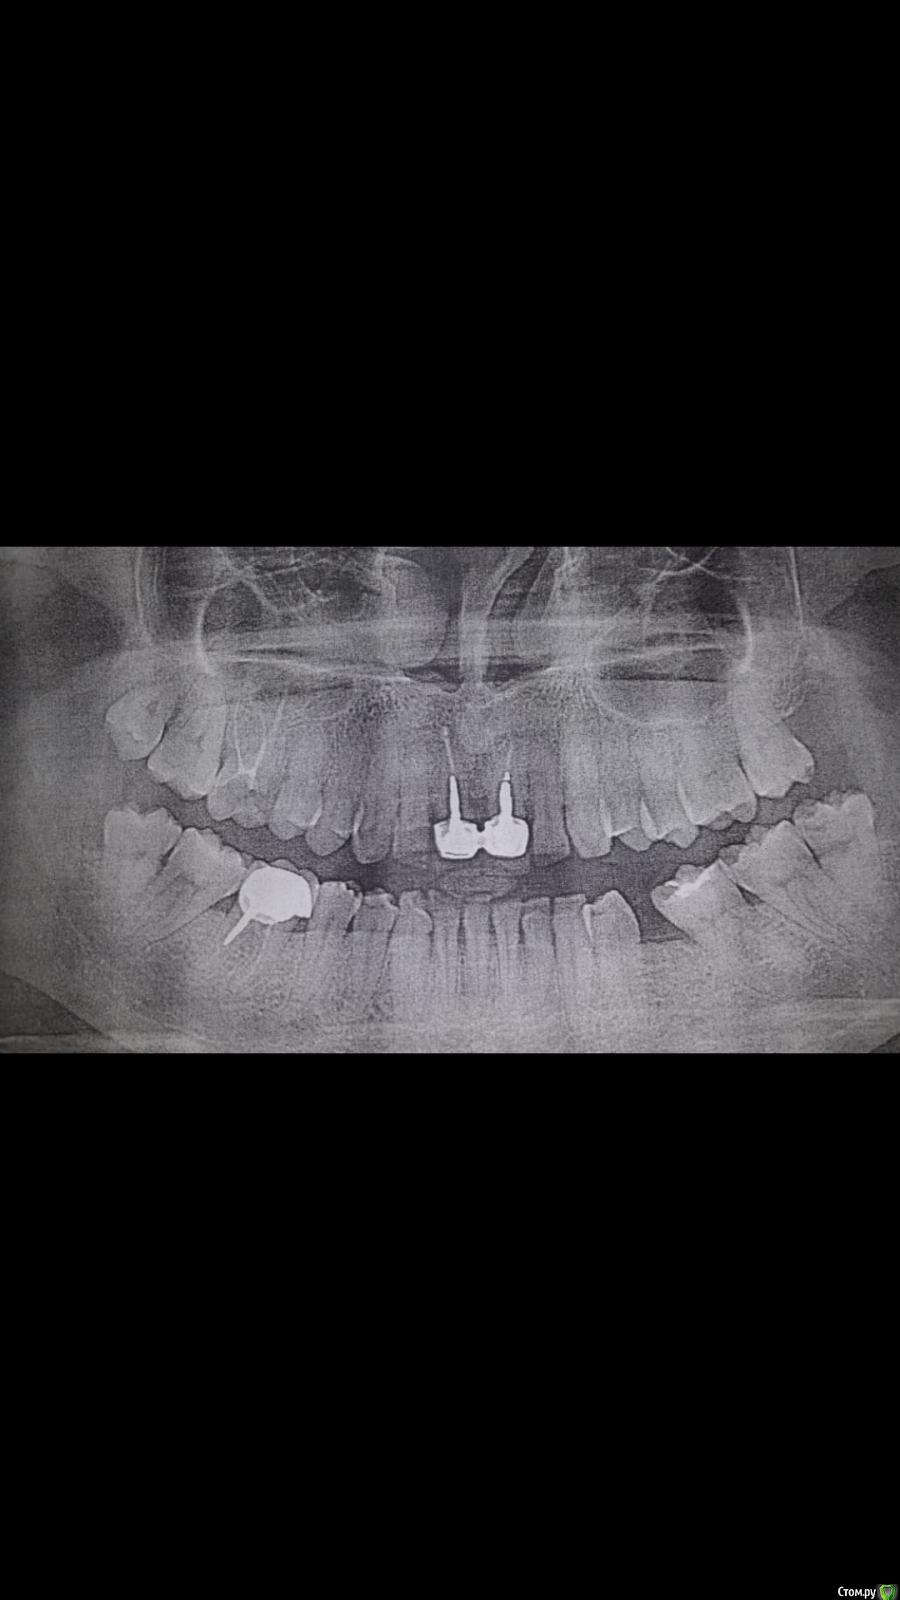

БабаКлава Опубликовано 17 апреля, 2019 Поделиться Опубликовано 17 апреля, 2019 (изменено) Подскажите пожалуйста план лечения и куда обратиться. Выпадают передние коронки со штифтами.Советуют ставить имплантанты или возможны еще варианты? Так же часто ноет нижняя сторона,возле коронки. Изменено 17 апреля, 2019 пользователем БабаКлава Ссылка на комментарий

БабаКлава Опубликовано 18 апреля, 2019 Автор Поделиться Опубликовано 18 апреля, 2019 Что лучше в моем случаи? Имплантант,мостовидный протез на 4 коронки ( с обточкой соседних ) или одномоментный адгезивный мостовидный протез . Ссылка на комментарий

kramer Опубликовано 19 апреля, 2019 Поделиться Опубликовано 19 апреля, 2019 Мостовидный протез на 4 единицы не получится, боковые резцы не выдержат, надо будет обтачивать ещё и клыки, так что это 6 единиц. Лучше 2 имплантата. Ссылка на комментарий

Дмитрий Л. Опубликовано 21 апреля, 2019 Поделиться Опубликовано 21 апреля, 2019 Нужен прицельный (маленький) снимок двух зубов. По возможности стремитесь сохранить зубы или удалить 1. Ссылка на комментарий

БабаКлава Опубликовано 22 апреля, 2019 Автор Поделиться Опубликовано 22 апреля, 2019 Ходила на консультацию, говорят могут зафиксировать коронки обратно, пока позволяют корни.В дальнейшем как придут в негодность уже ставить импланты на два .Год на поиски врача хорошего будет . Ссылка на комментарий

Дмитрий Л. Опубликовано 22 апреля, 2019 Поделиться Опубликовано 22 апреля, 2019 Идея компромиссная. Найдите хорошего ортопеда. Я бы рассмотрел вариант ортодонтического вытягивания резцов с последующим их нормальным протезированием, если на то есть условия. На форуме можно найти таких специалистов. Ссылка на комментарий